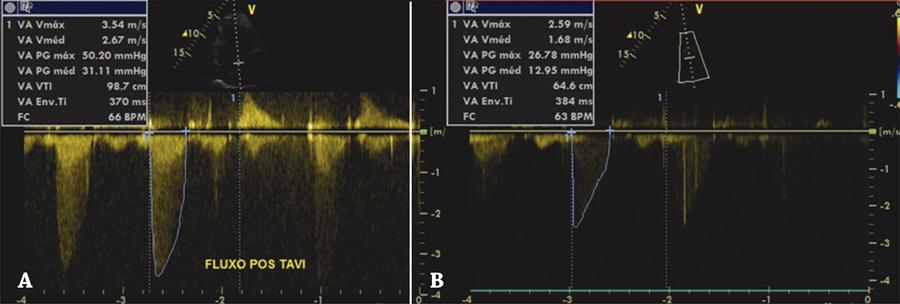

Figure 4

Aortic transvalvular gradient. (A) Echocardiographic control showing gradient after implantation of the transcatheter prosthesis; (B) major drop in gradient after balloon dilation.